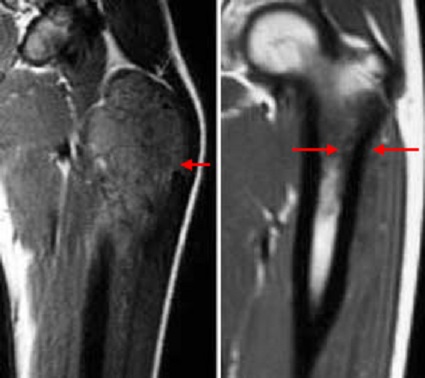

MRI of Ewing's sarcoma before and after chemotherapy

An MRI scan of a thighbone with Ewing sarcoma before (left) and after (right) chemotherapy treatment. The size of the tumor is much smaller after chemotherapy.